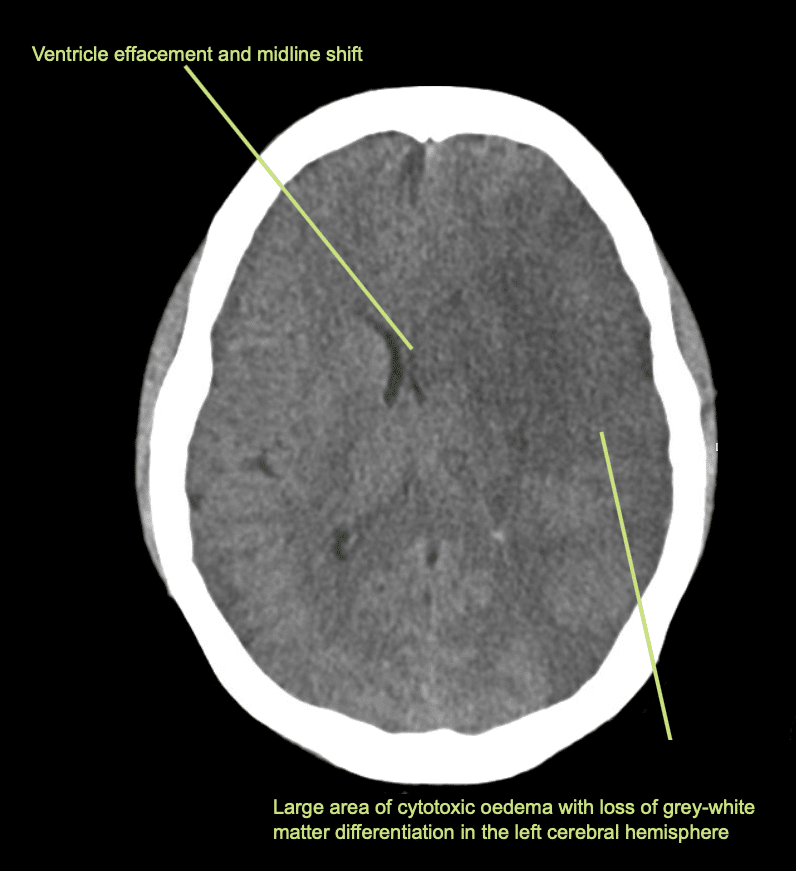

Vengono eseguiti una TAC cerebrale, un angiogramma e una scansione della perfusione cerebrale.

Descrivi e interpreta la TAC

Interpretazione della TAC